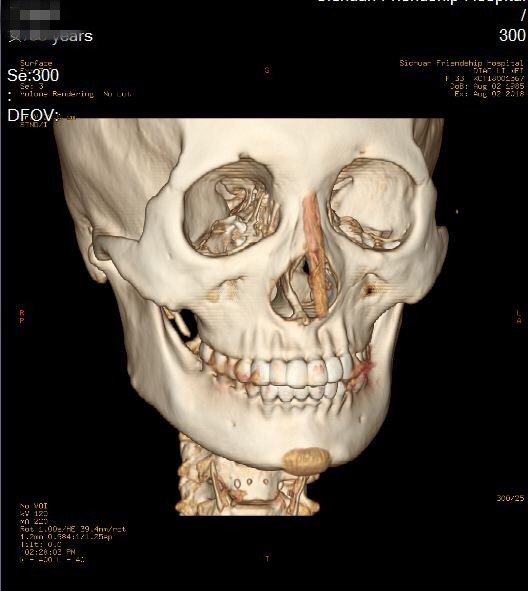

颧弓骨折一例

颧骨颧弓骨折